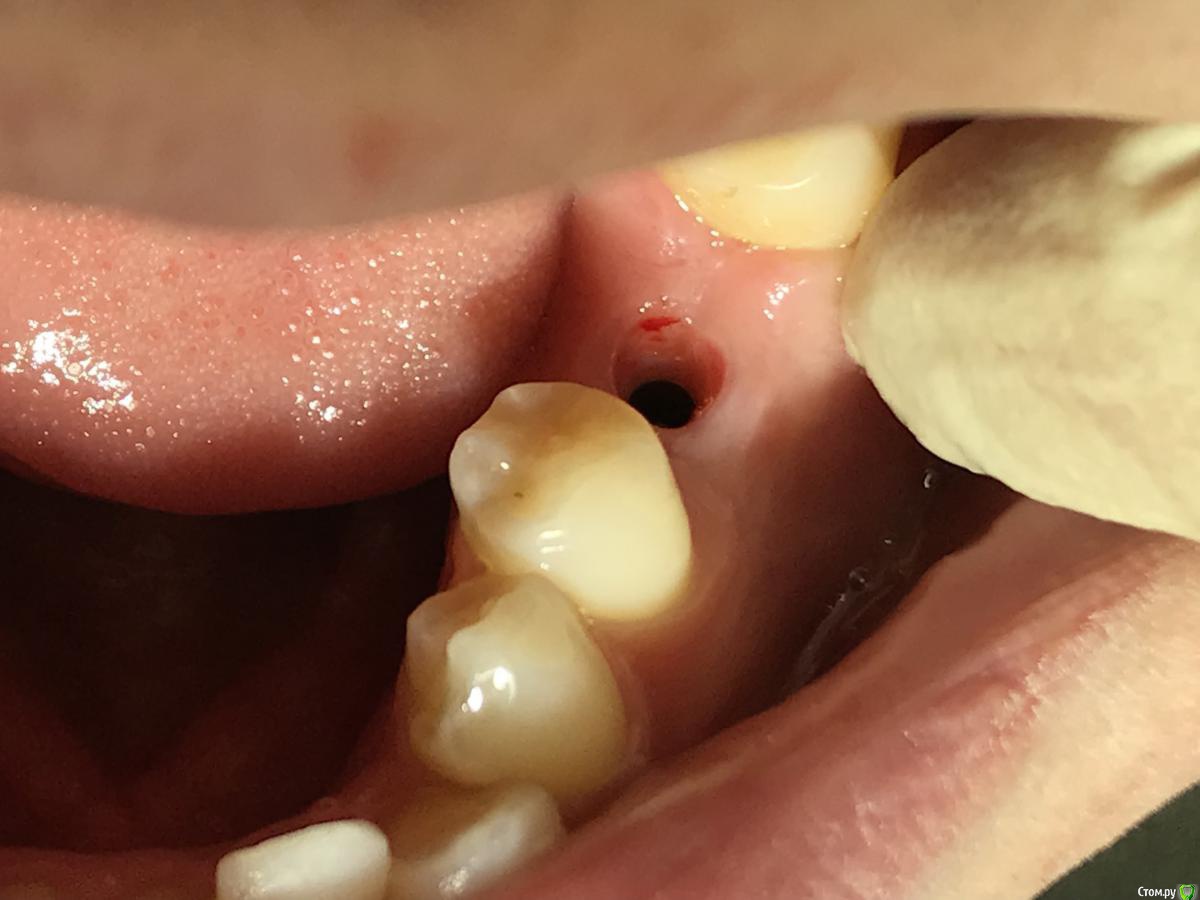

red_butler Опубликовано 22 января, 2020 Поделиться Опубликовано 22 января, 2020 Ранее не было аккаунта , коллега мой закидывал , зарегестрировался сегодняок, фото во рту покажите 1 Ссылка на комментарий

El_cucuy Опубликовано 22 января, 2020 Поделиться Опубликовано 22 января, 2020 ок, фото во рту покажитеХорошо , как раз завтра осмотр Ссылка на комментарий

El_cucuy Опубликовано 26 января, 2020 Поделиться Опубликовано 26 января, 2020 и? Ссылка на комментарий

Дмитрий Л. Опубликовано 26 января, 2020 Поделиться Опубликовано 26 января, 2020 Я бы не подсаживал, вроде 3 мм есть. 1 Ссылка на комментарий

red_butler Опубликовано 26 января, 2020 Поделиться Опубликовано 26 января, 2020 не вижу смысла работать с десной Ссылка на комментарий